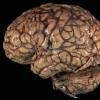

Meningitis

Meningitis, acute (2)